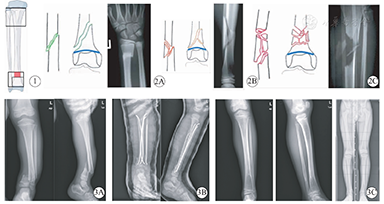

参照AO关于儿童长骨骨折的定位和分型[11]:先以胫腓骨远端骨骺板为底边向骨干方向作一大正方形,再以胫骨远端骨骺板为底边向骨干方向作一小正方形,两正方形在胫骨未重叠的红色区域即定义为干骺交界区(图1)。纳入标准:骨折线中点位于干骺交界区。

按照胫骨髓腔最窄处直径的33%~40%选择弹性钉并预弯,胫骨弹性钉直径2.5~3.5 mm,腓骨弹性钉直径2.0~2.5 mm;胫骨弹性钉预弯弧度是骨折处髓腔直径的4倍,弧度顶点位于钉头近端4~6 cm处,预弯弧度大于骨干骨折(骨干骨折预弯弧度为骨折处髓腔直径的3倍),目的是使俩钉头之间以最大的离散角度插入远折端,从而获得最大的支撑力和骨折稳定性;接着在C臂机透视下采用牵引,折顶等手法闭合复位胫骨骨折,当骨折端达到1/3以上的对位后,从胫骨近端内外侧各置入一枚弹性钉,当弹性钉头穿过骨折线达远折端时,调整钉头方向可进一步复位骨折,最后保持钉头相互之间最大的离散角度来固定骨折。胫骨用2枚弹性钉顺行固定后透视机下观察腓骨的情况,如已自行复位,无需再固定腓骨,如腓骨仍然移位大于60%,用1枚弹性钉逆行复位和固定腓骨(图3)。对于2例2枚弹性钉置入后仍然欠稳定的胫骨骨折,我们采用顺行置入第3枚胫骨弹性钉的方法以维持骨折的稳定性,2例骨折均为粉碎性(图3),1例合并开放性。弹性钉开路置入技术与骨干骨折相似,开放性骨折彻底清创后,复位置钉固定方法同闭合骨折。

4例出现并发症,其中2例患侧下肢过度生长,术后12个月时分别过度生长1.2 cm和1.4 cm,在最后一次随访中(分别是术后24个月和32个月),双下肢长度差缩小为0.7 cm和1.1 cm,在目前的随访中无步态异常等临床症状。2例发生骨折慢连接,1例为7岁患儿,车祸伤,干骺交界区开放性骨折,GustiloⅠ度,简单粉碎性骨折;另1例14.8岁青少年,坠落伤,复杂粉碎性骨折;拆除石膏后采用支具保护下负重,通过纵向挤压骨折断端来促进骨折愈合,术后10个月X线片显示临床愈合(典型病例影像学资料见图3)。

2.对于胫骨远端干骺交界区严重骨折,以往认为该部位骨折不是ESIN固定的适应证。理论上,在干骺交界区,ESIN固定强度不可靠,因其没有利用到预弯的弹性钉在髓腔内交叉产生的交叉应力;因此以往较多采用钢板内固定或外固定支架治疗。传统钢板可解剖复位,且固定可靠,但一般需切开复位后置入,手术创伤较大,影响骨折部位血运;近年来逐步开展了经皮微创加压锁定钢板(MIPO)在青少年中的应用[8,9,10],手术创伤较小,适用于粉碎性骨折和不稳定的大斜形骨折,但仍然存在钢板应力遮挡,过度生长及治疗费用高等问题;外固定支架的应用文献也有许多报告,对骨折局部血运影响小,可以避开骨折部位置钉,更适合于开放性骨折和严重粉碎性骨折[6,7],但护理难度高,并发症相对较多,如针道感染、骨骺损伤、延迟愈合、再骨折、肢体过度生长等。2014年Cravino等[12]首次报道使用ESIN治疗18例胫骨远干骺端骨折,结果同骨干骨折一样微创有效,并发症少;如果把胫骨远干骺端分为两部分(图1),一部分为靠近骨干的干骺交界区(干骺端近端区域),另一部分则为邻近骺板的干骺端远端区域;我们推荐ESIN应用于干骺近端区域—即干骺交界区的严重骨折,而不推荐ESIN用于邻近骺板的干骺远端区域。因为不等同于ESIN治疗肱骨近端干骺端骨折,多位学者[13,14]报道钉头可以穿过肱骨近端骺板,置入骨骺固定骨折而不产生骨骺损伤生长紊乱;我们知道胫骨远端骨骺生长塑形潜力远不及肱骨近端,更容易在外伤后出现骨桥骨骺早闭等生长异常情况,所以在胫骨远端置钉时钉头要避免伤及骺板。如果用ESIN在不置入骨骺的情况下固定胫骨远端邻近骺板的骨折,就会显得力不从心,缺乏足够的固定效果。同样对于干骺交界区的大斜形骨折,严重粉碎性骨折和Gustilo Ⅲ度开放骨折,我们也不推荐使用ESIN。